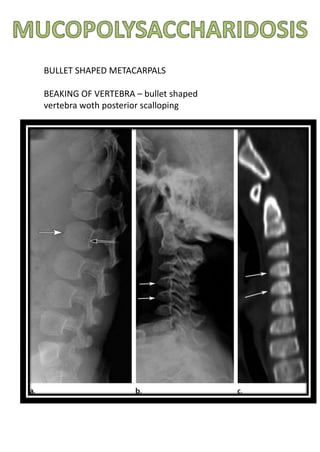

BULLET SHAPED METACARPALS

BEAKING OF VERTEBRA – bullet shaped